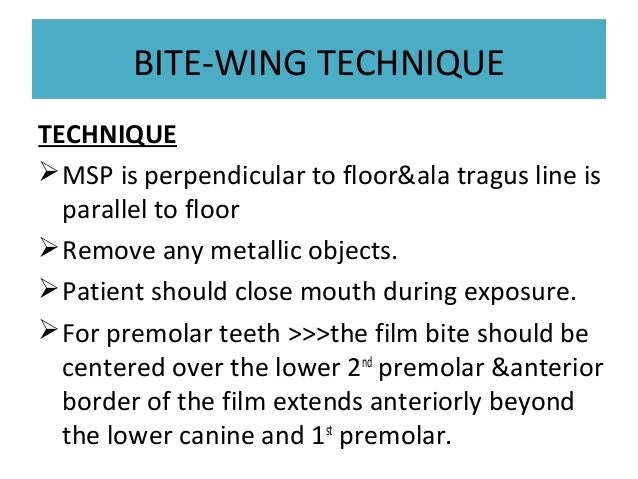

Tragus of the ear must be aligned with the plastic guides ala tragus line should be 50 from level positioning the patient position the patient panoramic lead apron must be used position apron high in front to protect the thyroid apron should be lower in back to expose the neck. Discussion most panoramic x ray machines use the ala tragus line for patient positioning whereas a few use the orbito meatal line. Ala tragus line is one of the common extra oral soft tissue land mark utilized in dental clinics for occlusal plane orientation. Here the occlusal plane should be mildly curved upward to make a smile like line.